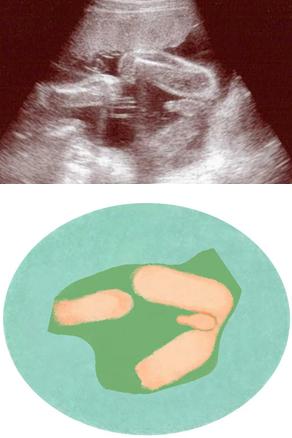

妊娠23週ころの超音波写真

早ければ外性器がわかるようになります

外性器の違いが現れるのは11週ごろですが、超音波ではっきり確認できるのは18週以降。赤ちゃんは羊水の中でぐるぐる回っているので、体位により性別がわかることも。写真は男の子。